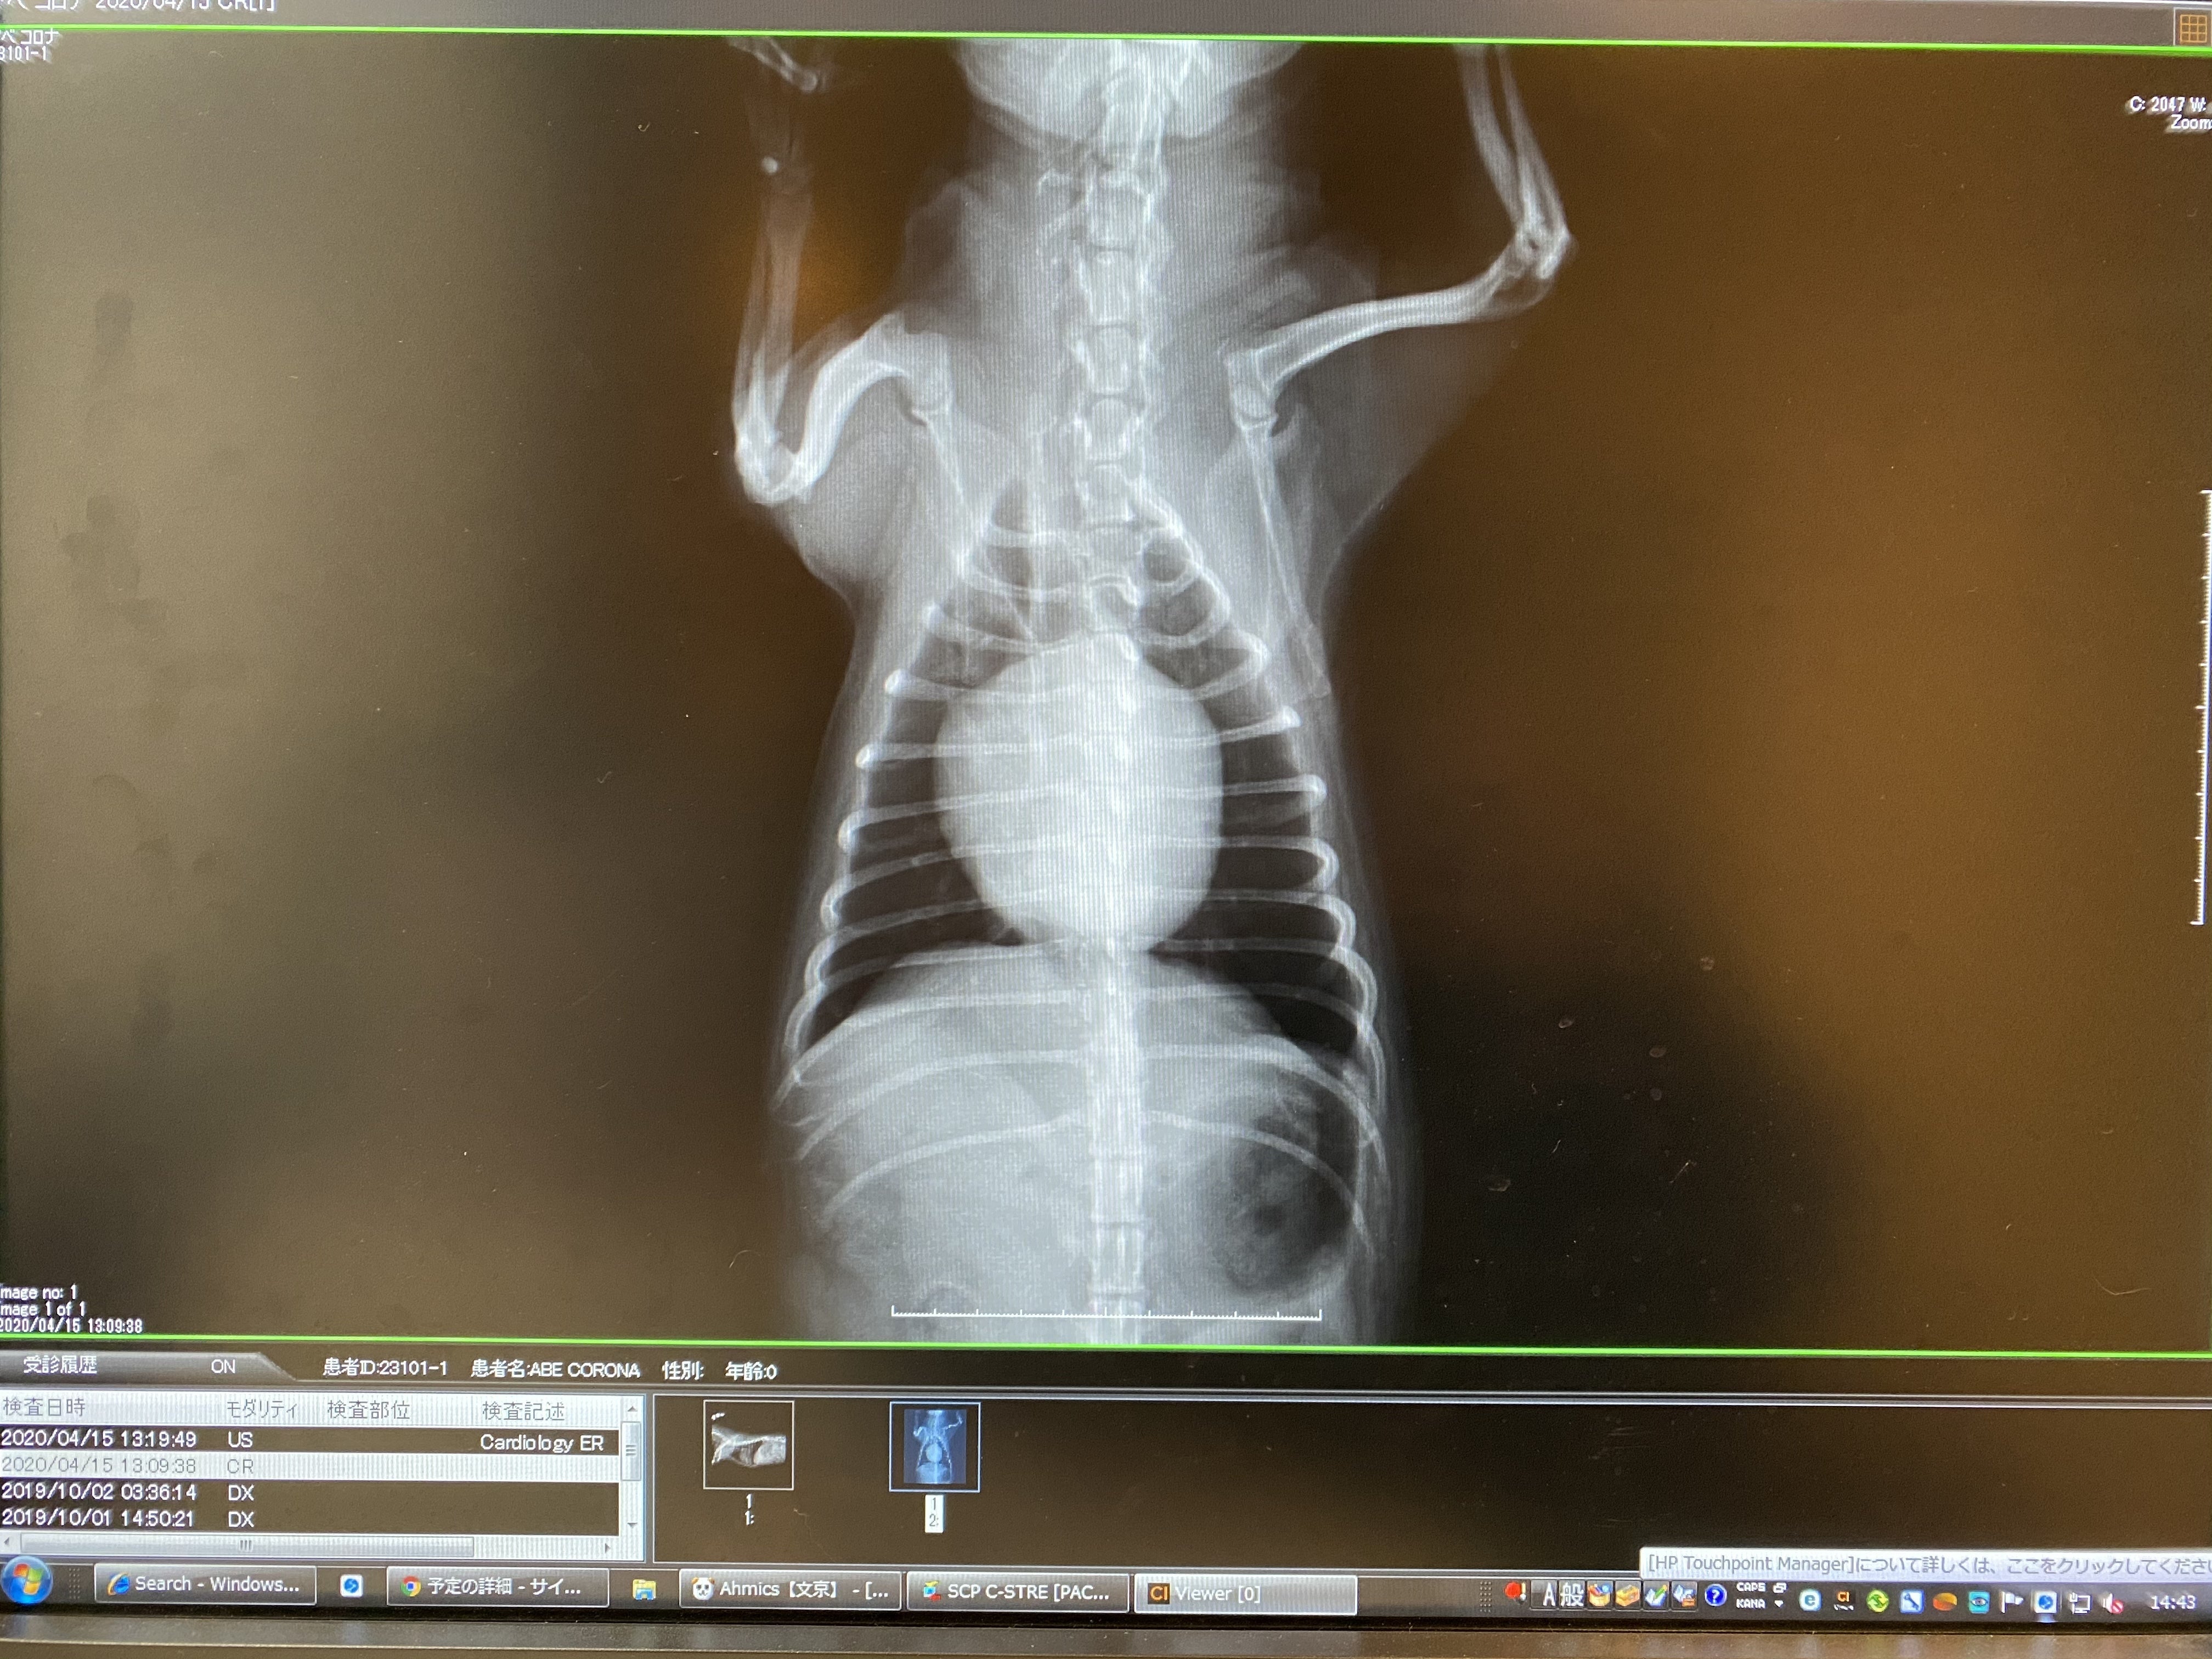

真ん中の丸く膨れ上がってるのが心臓です

大きさは普通のチワワの2~3倍で、気道を圧迫していて苦しそうに咳をします。

心臓が気道を圧迫しているのが分かります

心臓の弁は反対側にそり返るほど壊れていて、血液の逆流は8割、心臓はパツパツで負担がかかりすぎているため、できる限り早い手術を勧められました。